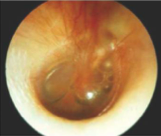

Otitis media with effusion (OME)

otitis media with effusion

fluid in the middle ear space without signs/symptoms of acute ear infection

OME, bubbles